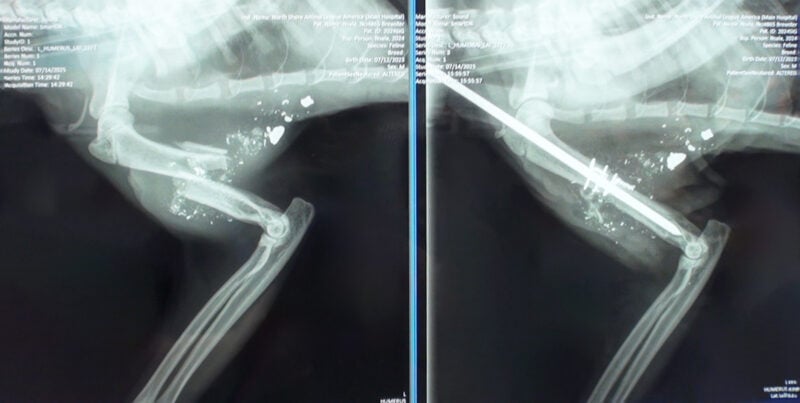

X-rays revealed a shattered humerus – the bone in his upper front leg – along with metal fragments embedded in the tissue, indicating a gunshot wound, most likely from a pellet gun. The bullet tore through his leg and exited near his armpit, dangerously close to critical nerves that control limb movement.

Initially, amputation seemed like the only treatment option. But Animal League America Chief of Veterinary Staff Dr. Mark Verdino thought differently, and Brewster was immediately transported to our Pet Health Centers. “I always want to try and save the limb in these situations if we can,” he said. “No question this was a complex, delicate surgery. The bone was in several pieces, and we ended up having to place a metal rod down the center to realign and stabilize it.”